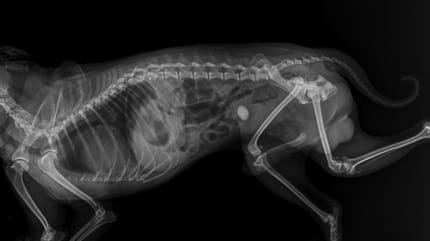

Katze hat Blasensteine: Diagnose

Für den Tierarzt ist eine Urinprobe der Katze wichtig, um eine Diagnose stellen zu können. Es gibt spezielle Katzenstreu, um eine Urinprobe aufzufangen – für Halter von Freigängern kann die Urinprobe zu einer Herausforderung werden. In manchen Fällen muss der Urin in der Tierarzt-Praxis ausmassiert werden.

Der Tierarzt untersucht den Harn auf Entzündungen sowie mit dem Mikroskop. Harnsteine sind unter dem Mikroskop ebenso sichtbar wie im Ultraschall. Es ist wichtig zu wissen, welche Harnsteine die Katze hat. Denn ein urinansäurendes Futter, das Struvitsteine auflöst, begünstigt Kalziumoxalat-Steine.